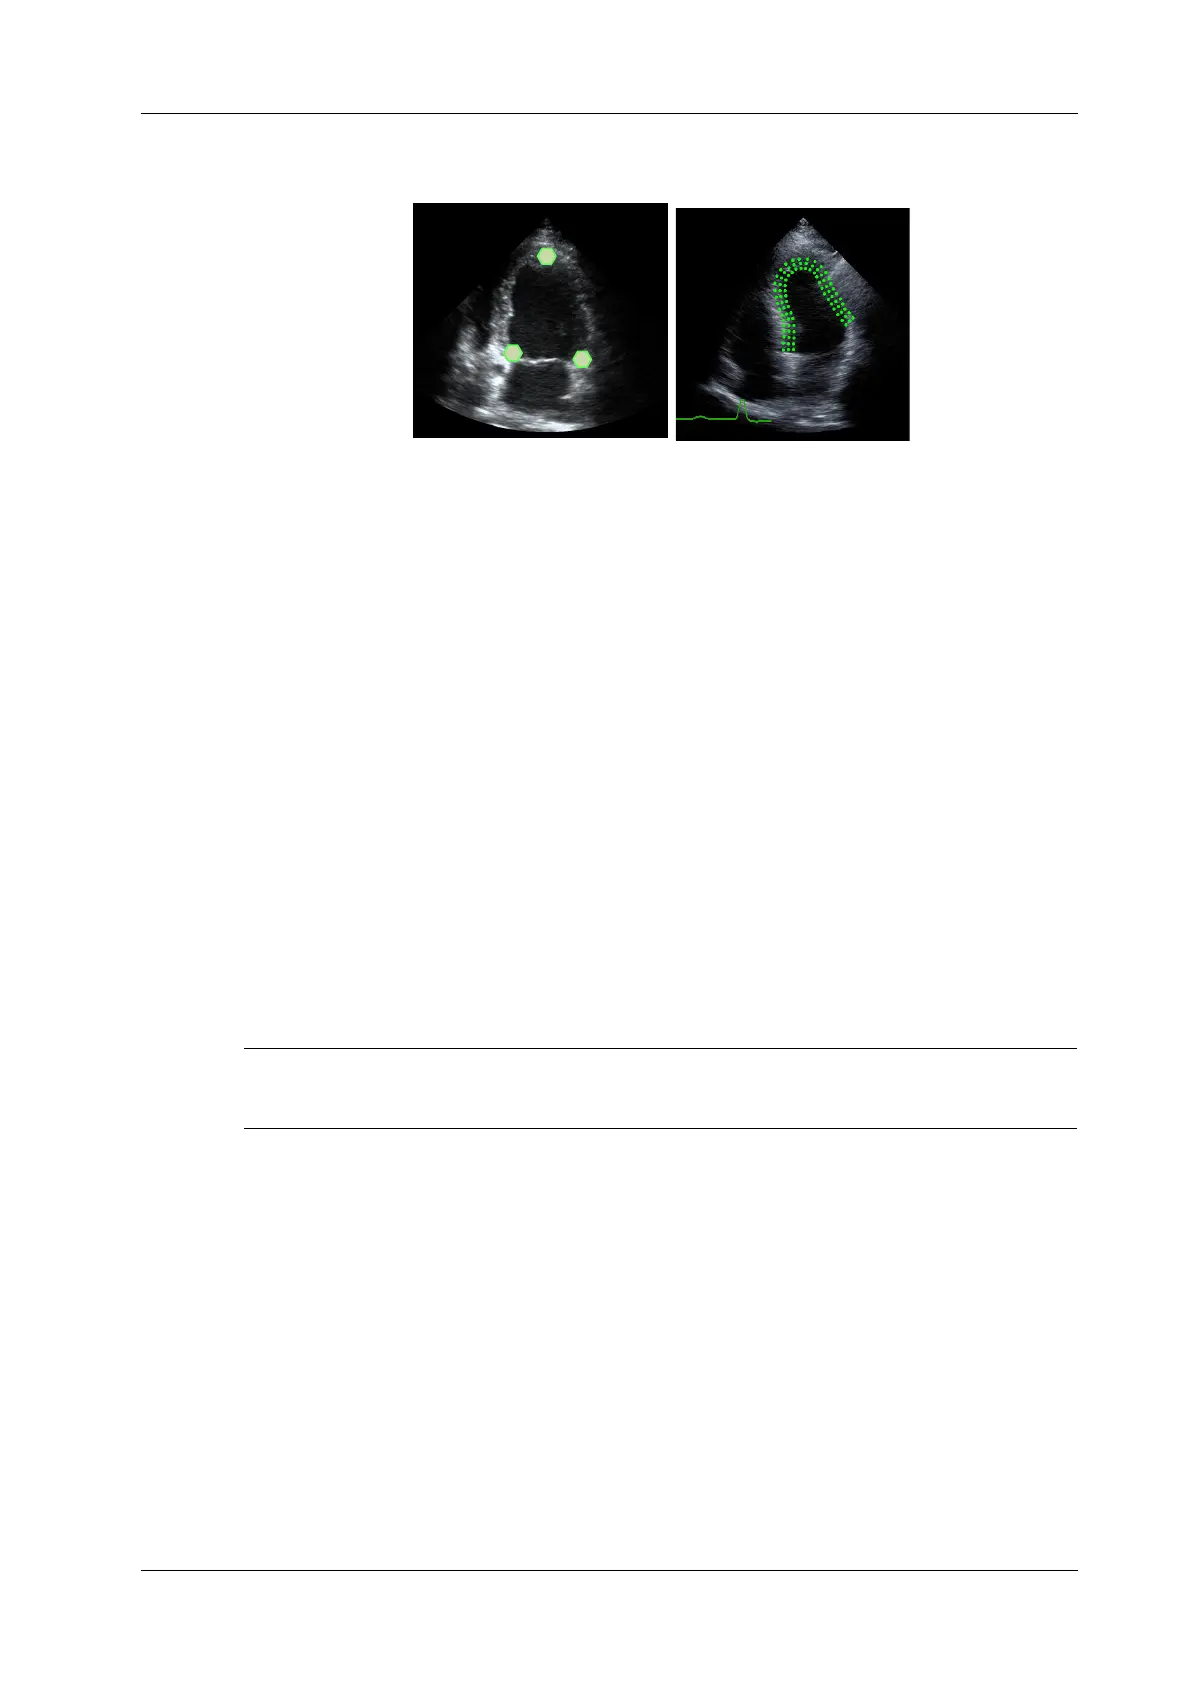

As shown in the following figure, after operation by tapping to place 3 points on the image, the

system generates the trace automatically.

View Selection

Before tracing, tap the corresponding button to select for the view.